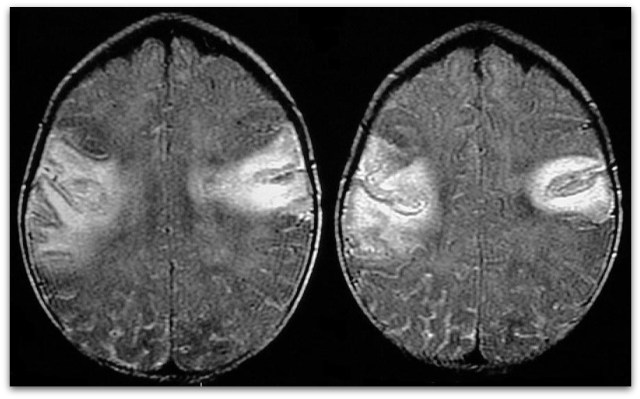

Информация о диссеминированном рассеянном энцефаломиелите